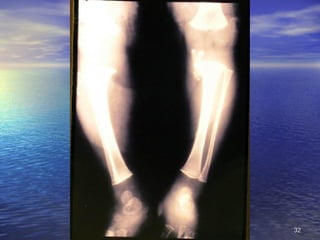

2. Signos Circunstanciales No se encuentran siempre, sino que están condicionados a causas ambientales o ecológicas, no específicas: alteraciones de la piel y faneras, lesiones oculares, de lengua, óseas, de músculos y ligamentos, de aparato digestivo, alteraciones hematológicas, neurológicas, edema

2. Signos CircunstancialesNo se encuentran siempre, sino que están condicionados a causas ambientales o ecológicas, no específicas: alteraciones de la piel y faneras, lesiones oculares, de lengua, óseas, de músculos y ligamentos, de aparato digestivo, alteraciones hematológicas, neurológicas, edema